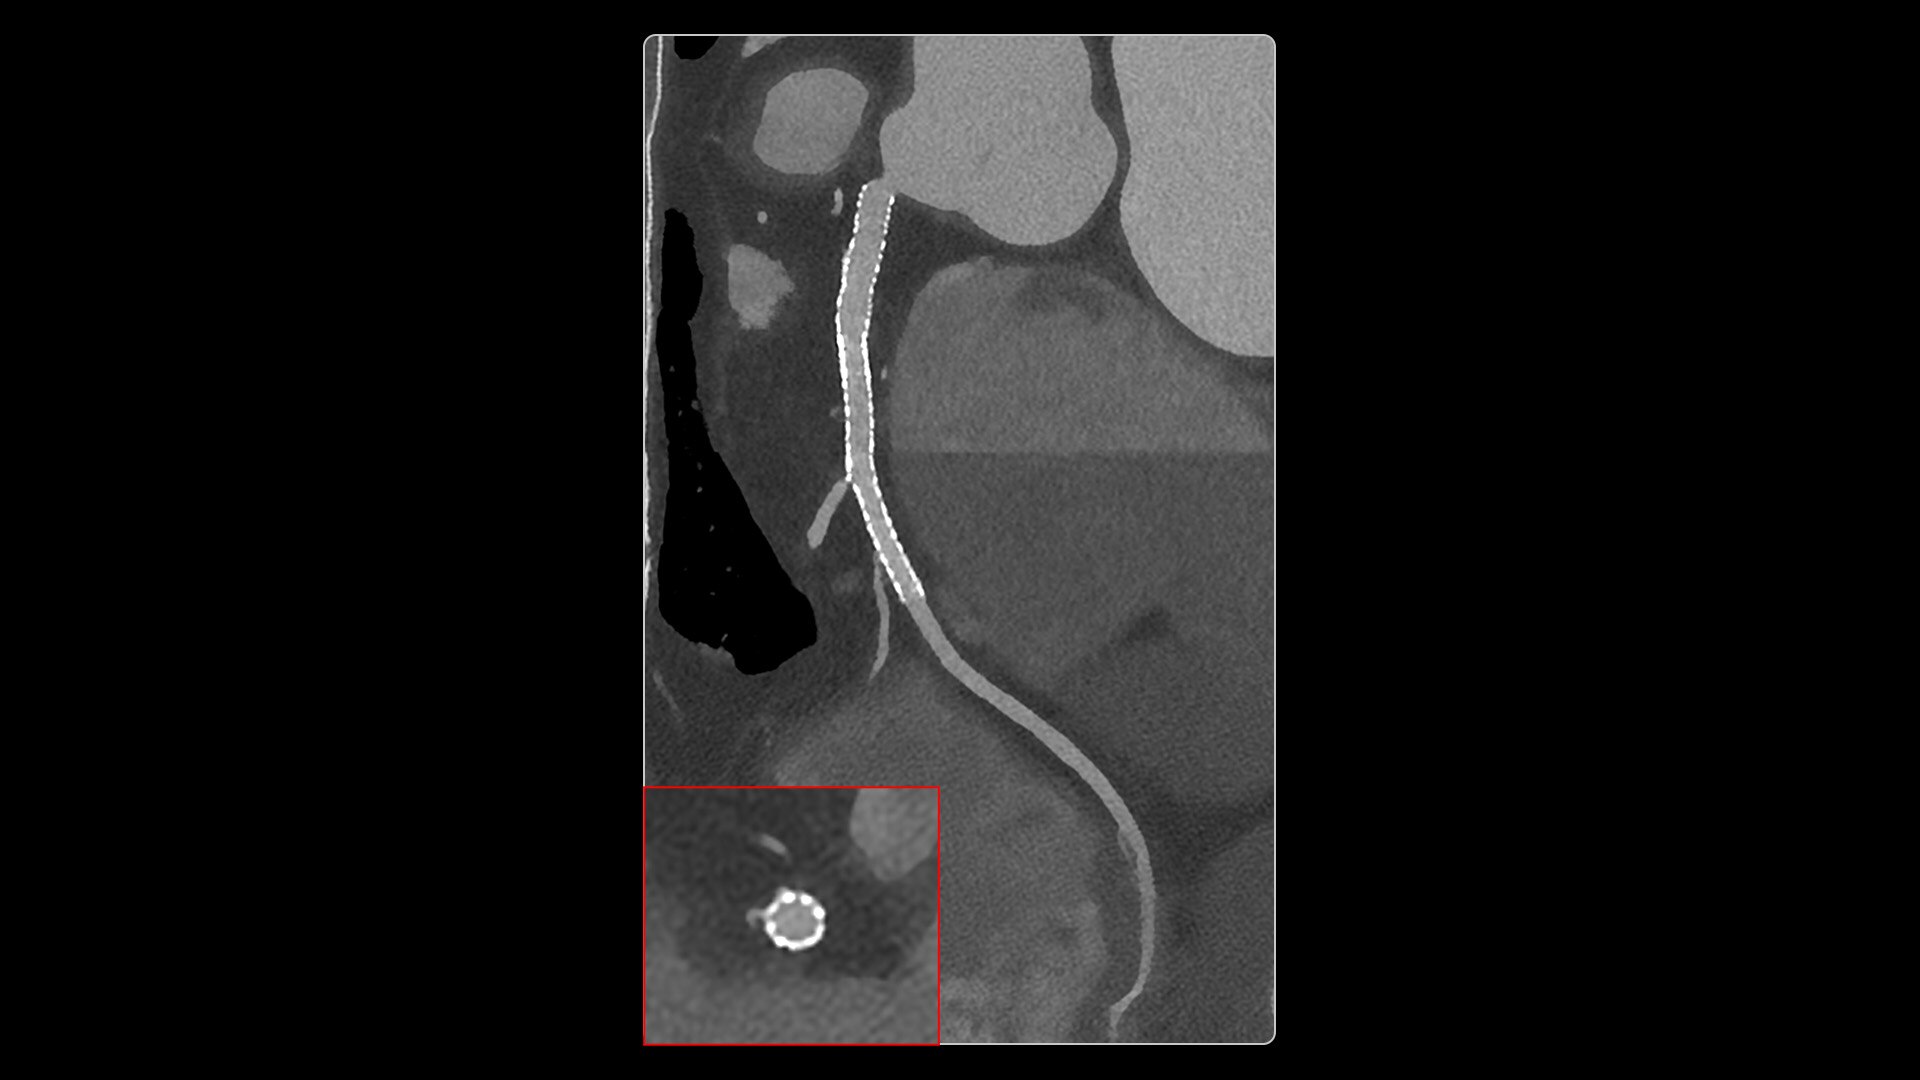

Photonova Spectra provides wide coverage in ultra-high definition imaging with exceptional acquisition speeds, designed to allow you to see your patient’s anatomy in exquisite detail.

With ultra-high spatial resolution scanning capability, Photonova Spectra is designed to help you see incredibly fine details, such as coronary plaque delineation, small microvascular vessels and even tiny structures of the inner ear.

Experience our industry-leading 8 cm detector coverage, combined with up to 0.23 sec rotation speed and ultra-high sampling rates featuring a 50 cm field of view (FOV) in all scan modes. This enables wide-coverage ultra-high definition imaging with reduced organ movement for exceptional image clarity.